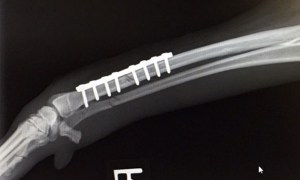

Take your Italian Greyhound to your Vet immediately if he/she has a suspected leg fracture / broken leg. In most cases, a Vet should: Surgery Depending on the type of fracture, different forms of treatment might be recommended. Most are best treated with an operation.… Read More >